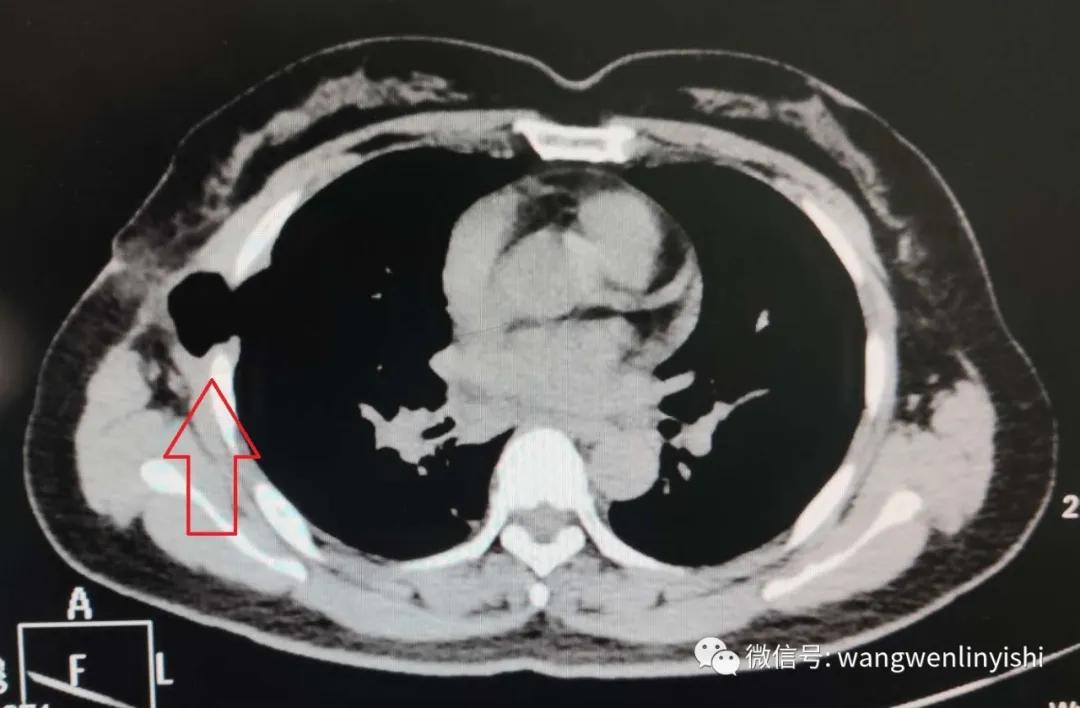

患者为中年女性,因肺部小结节在某院接受胸腔镜手术,术后患者出现剧烈咳嗽,经对症处理效果不佳入我院。行CT检查,发现右侧手术切口处有明确胸壁缺损,肺组织嵌入缺损,形成切口疝。患者诊断明确,为胸部手术后的胸壁缺损,切口疝。考虑到缺损较大,我们采用保守方法做处理。经一周治疗,症状消失。再次复查CT,肺组织回复胸腔,但胸壁缺损尚存。考虑到缺损较小,不做特殊处理,病人出院。

(右侧胸壁缺损,肺组织疝入缺损)